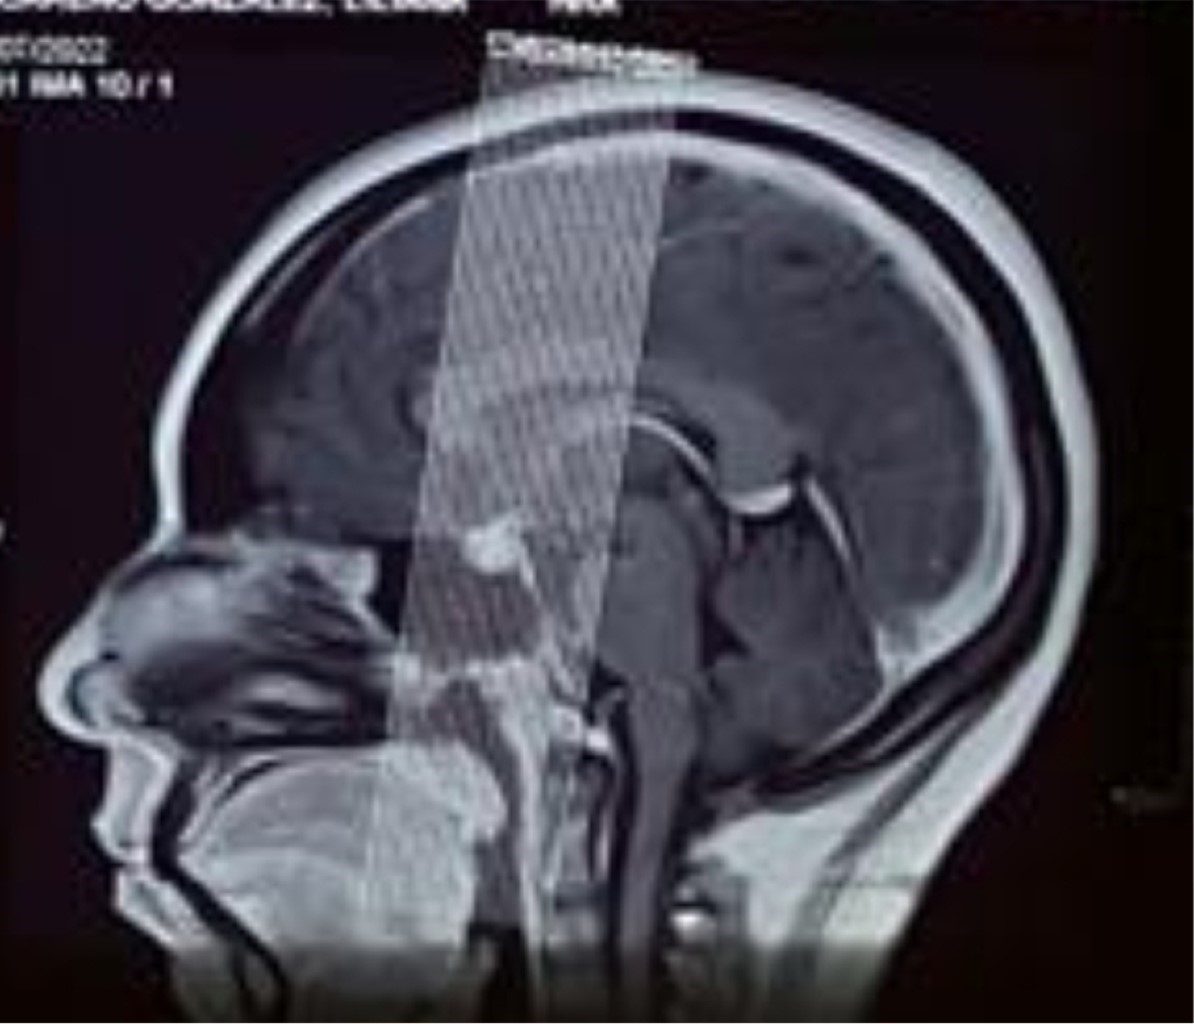

Granulomatosis with polyangiitis is a rare and serious autoimmune condition. In addition to typical symptoms, some patients may present invasion of the central nervous system, manifested as central diabetes insipidus. However, this complication occurs in less than 1%, making it a diagnostic challenge. We report the case of a 33-year-old patient previously diagnosed with granulomatosis with polyangiitis following a bout of alveolar hemorrhage, who started treatment with azathioprine and prednisone. Upon tapering off prednisone, she developed temporal headache, polyuria, and polydipsia. We present the diagnostic approach of a patient with the main clinical feature of polyuria. The presentation of cases with atypical progression is essential to improve understanding and management of this rare but significant condition in the context of granulomatosis with polyangiitis.

Figure 2